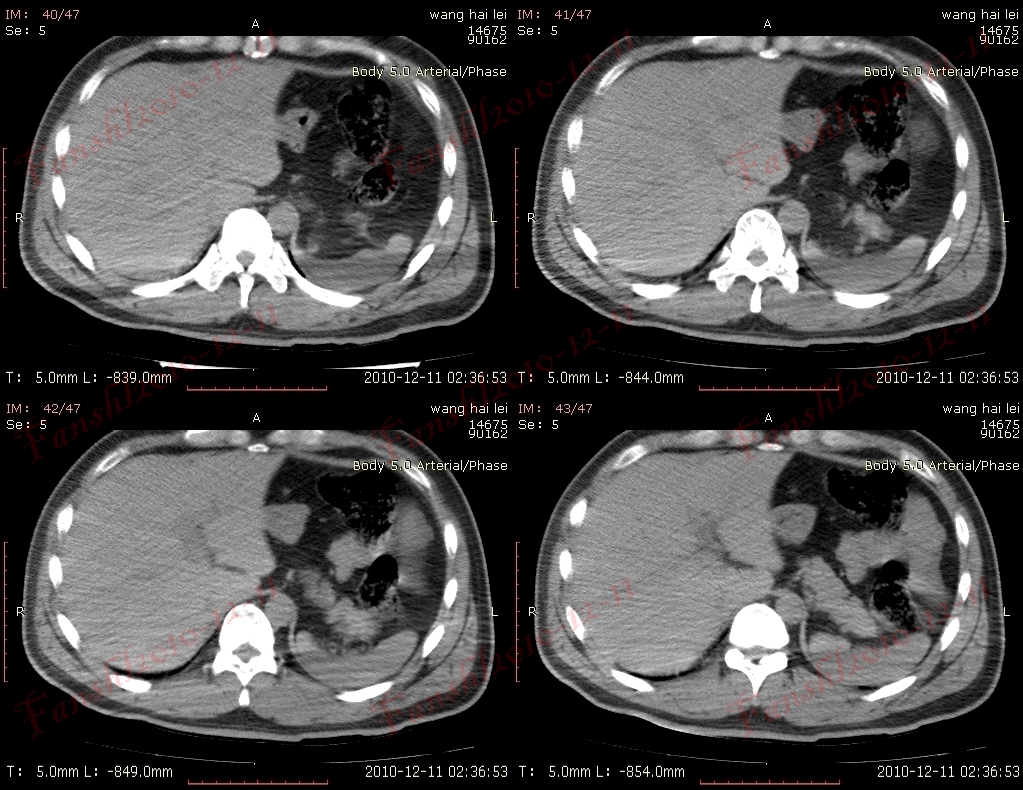

有多个名称,分别是:环靶征;双靶征;环征;双环征;三环征等。肝脓肿CT增强扫描的典型表现,因呈靶环状而得名。表现为肝内囊样低密度肿块病灶,边缘多数较模糊,脓肿周围往往出现不同密度的环形带(环征或靶征),增强扫描脓肿壁呈不同程度的环状强化,脓肿壁可为单环、双环或二环。

靶征是肝脓肿的典型征象,是脓肿形成期的表现。此期脓腔液化坏死彻底,脓肿壁可为单环,双环或三环,单环代表了脓肿壁,其周围水肿不明显;双环的内环代表脓肿壁,外环代表周围水肿带;三环表明脓肿壁由三层构成,外层(中环)为纤维肉芽组织,强化最明显,内层(内环)由炎性组织构成,强化不如外层纤维肉芽组织。肝脓肿靶征的出现代表着一定阶段病变的病理过程,为肝脓肿的特征性表现,对诊断很有价值。

大多数学者把肝脓肿的脓肿形成期CT表现认为是典型表现,表现为肝内囊样低密度肿块,病灶边缘多数较模糊,脓肿周围往往出现不同密度的环形带(环征或靶征),增强扫描脓肿壁呈不同程度的环状强化;少数患脓肿内出现气体,此时可肯定诊断。

CT平扫肝脓肿可发生于各肝叶,但以右叶多见,可单发或多发,大小不等。肝内低密度占位,CT值10~35Hu,边界多不清楚或部分模糊,脓肿周围壁较厚。病变组织坏死越完全,其密度越低、越均匀。如慢性肝脓肿,边缘清楚,CT值接近于水肿的密度,而且有时周围可见一圈高于脓腔低于正常肝组织的低密度水肿环,因而易于诊断。若脓肿内有气一液平面,表示液化比较完全,伴产气菌感染所致,通常被认为是诊断肝脓肿的特异性征象。

增强扫描使病灶内部结构、病灶边缘与正常肝组织的关系显示得更清楚。门脉期可显示肝脓肿较典型的CT征象,为典型三层病理改变增强后的CT表现,中心坏死区无强化,中间层为介于液化坏死区与正常肝组织之间的低密度带晕带环,外围层与正常组织分界模糊。慢性期由于脓肿周围形成血管丰富的结缔组织包膜,脓肿壁显著环形强化,其密度高于肝组织。环绕脓腔的为强化环,可以是单环、双环甚至三环。3个环相当于脓壁的3种病理结构:水肿、纤维肉芽组织和炎性坏死组织。如果3种结构存在则出现三环,否则出现双环或单环。